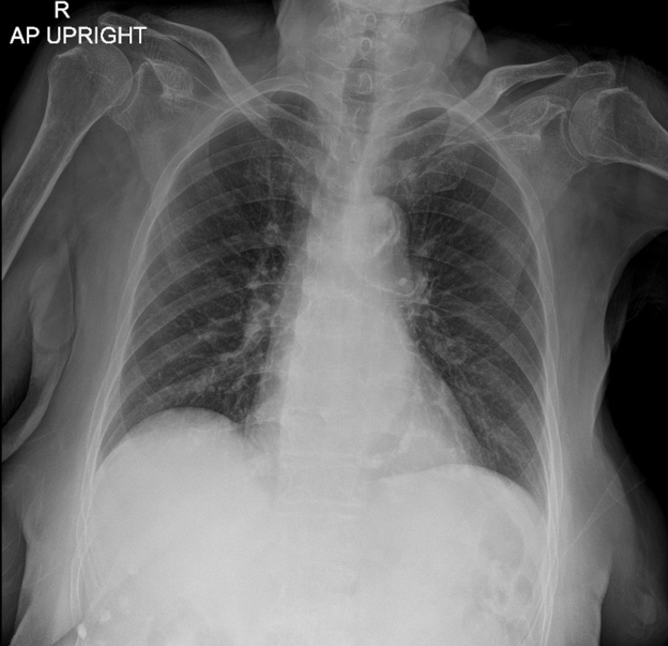

An 84-year-old female with underlying disease of paroxysmal atrial fibrillation and dyslipidemia was admitted with non-ST elevation acute coronary syndrome to the provincial hospital. Her blood pressure was 128/83 mmHg, her heart rate was 68 beats per minute. The coronary angiography showed left main disease with double vessel disease. The patient refused to CABG due to risk of operation and elderly age. She was referred for PCI at our center.

The initial electrocardiogram showed a sinus rhythm rate of 60 beat per minute with horizontal ST depression in V2 to V4. The transthoracic echocardiography demonstrated a left ventricular ejection fraction of 58% with anterior and anteroseptal wall hypokinesia from mid to apex and no significant valvular abnormalities. Basic laboratory results were normal.